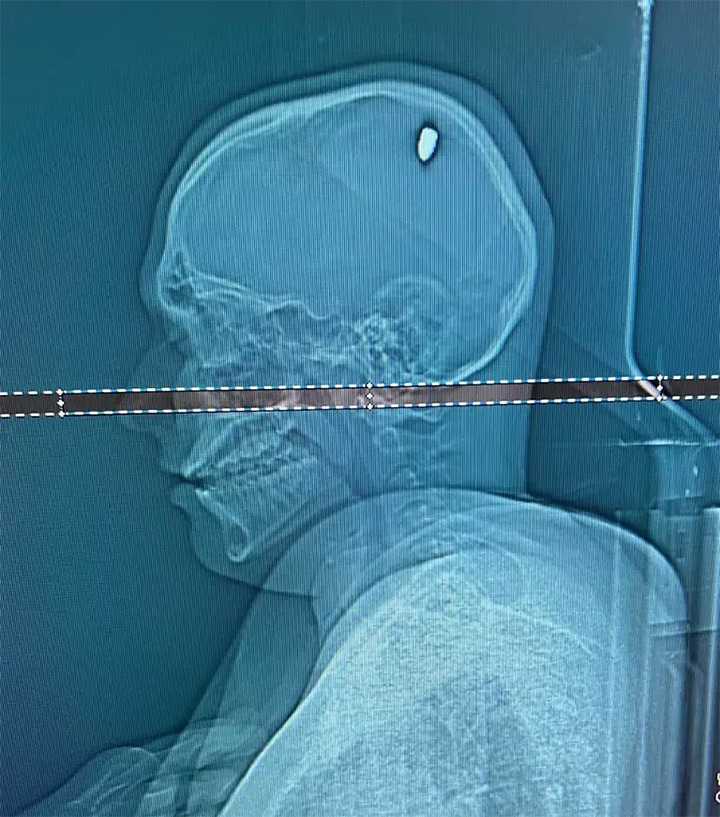

Θορυβημένος, ο Mateus έφθασε στο νοσοκομείο όπου οι γιατροί διαπίστωσαν ότι είχε μια σφαίρα 9mm στο κεφάλι του.

Η σφαίρα συμπίεζε τον εγκέφαλο σε μια περιοχή πλησίον αυτής που είναι υπεύθυνη για την κίνηση του δεξιού χεριού, εξήγησε ο νευροχειρουργός Flávio Falcometa. Αυτό οδήγησε στο να αντιδρά ο εγκέφαλος με κινήσεις που έμοιαζαν με επεισόδια σπασμών.

Ο γιατρός δήλωσε ότι ο ασθενής ήταν πολύ τυχερός που δεν είχε πιο σοβαρή βλάβη όπως παράλυση του χεριού ή του σώματος.

Ο Mateus στη συνέχεια υποβλήθηκε σε δίωρη εγχείρηση για την απομάκρυνση της σφαίρας, κατά τη διάρκεια της οποίας θα μπορούσε να κινδυνεύσει από αιμορραγία, μηνιγγίτιδα, ακόμα και θάνατο, σύμφωνα με τη μητέρα του.

Οι γιατροί με επιτυχία αφαίρεσαν τη σφαίρα χωρίς να προκληθεί βλάβη και η αστυνομία ξεκίνησε έρευνα για τον πυροβολισμό.